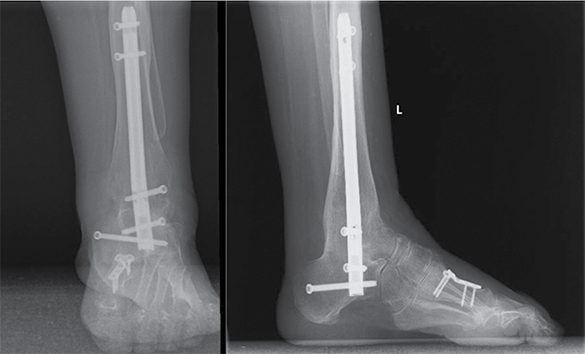

56 m. pacientė atvyko į Lietuvos sveikatos mokslų universiteto ligoninę Kauno klinikas (LSMUL KK) dėl metus trunkančio čiurnos ir pėdos skausmo bei deformacijos. Prieš metus pacientei diagnozuota CMT liga. Rentgeno vaizduose matyti kairės čiurnos cavovarus deformacija, šokikaulio panirimas, čiurnos sąnario artroziniai pakitimai, egzostozės po lateraline kulkšnimi. Kompiuterine tomografija nustatyta III stadijos čiurnos sąnario artrozė ir II stadijos subtalarinio sąnario artrozė. Objektyviai vertinant, pėdos plantarinė fleksija ‒ 20°, dorsifleksija ‒ 5°. Skausmas pagal skausmo skalę (VAS) įvertintas 8 balais (10 ‒ labai stiprus skausmas, 0 – skausmo nėra). Remiantis Europos čiurnos ir pėdos draugijos sukurta funkcijos vertinimo skale (EFAS), čiurnos ir pėdos funkcija įvertinta 4 iš 24 galimų balų (24 balai ‒ gera čiurnos ir pėdos funkcija). Taikant Amerikos pėdos ir čiurnos ortopedų draugijos (AOFAS) čiurnos ir pėdos funkcijos vertinimo sistemą, įvertinimas siekė 23 balus iš 100 galimų (100 balų – gera funkcija). Pacientei atlikta TTC artrodezė intrameduline vinimi, I padikaulio uždaro kampo osteotomija, koreguota padikaulio ašis, ji fiksuota rakinama plokštele ir sraigtais. Po operacijos rekomenduota 2 savaites laikyti koją pakėlus, 15 savaičių dėvėti čiurnos įtvarą, išėmus siūlus, dar 6 savaites dėvėti kompresinę kojinę, 12 savaičių neminti kojos. Po 10 savaičių pacientė turėjo atvykti kontrolinio vizito ir pradėti didinti krūvį. Reabilitacija pradėta praėjus 10 savaičių. Po metų rentgenologinėse nuotraukose matyti čiurnos ir subtalarinio sąnario ankilozė, kaulų ir vinies padėtis gera. Pagal VAS skausmas sumažėjo iki 2 balų, pagal EFAS jis vertinamas 18 balų, pagal AOFAS ‒ 66 balais.

2 pav. Kairės čiurnos ir pėdos tiesinė ir šoninė rentgenogramos po 6 metų

Po trejų metų pacientė atvyko dėl dešinės čiurnos ir pėdos skausmo, tinimo ir deformacijos. Konservatyvus gydymas buvo neveiksmingas. Vertinant objektyviai: pėdos dorsifleksija ‒ 5°, plantarinė fleksija ‒ 25°, VAS ‒ 8, EFAS – 5, AOFAS – 38 balai. Rentgeno nuotraukose matyti dešinės čiurnos ir pėdos cavovarus deformacija, pradiniai artroziniai čiurnos ir subtalarinio sąnarių pakitimai. Nutarta atlikti dešinio kulnakaulio gumburą lateralizuojančią osteotomiją, subtalarinio sąnario artrodezę sraigtais, Hoke metodika pailginti Achilo sausgyslę ir atlikti plantarinės fascijos fasciotomiją. Nurodyta 8 savaites neminti kojos, 10 savaičių dėvėti čiurnos įtvarą, pašalinus siūlus, dar 6 savaites naudoti kompresinę kojinę. Po 3 savaičių rekomenduota mankštinti koją atliekant pėdos fleksiją ir ekstenziją. Reabilitaciją planuota pradėti po 10 savaičių. Po metų pacientė atvyko dėl išliekančio dešinės čiurnos ir pėdos skausmo, tinimo. Rentgeno nuotraukoje matyti progresuojanti dešinės čiurnos sąnario artrozė ir varus deformacija. Pėdos fleksija ir ekstenzija išliko tokia pati, čiurnos sąnarys nestabilus. Nuspręsta atlikti TTC artrodezę intrameduline vinimi. Praėjus dvejiems metams, rentgenologinėse nuotraukose matyti čiurnos ir subtalarinio sąnario ankilozė, kaulų ir vinies padėtis gera. Pagal VAS skausmas sumažėjo iki 2 balų, pagal EFAS jis vertinamas 21, pagal AOFAS – 71 balu.

3 pav. Dešinės čiurnos ir pėdos tiesinė ir šoninė rentgenogramos prieš operaciją

4 pav. Dešinės čiurnos ir pėdos tiesinė ir šoninė rentgenogramos po dvejų metų